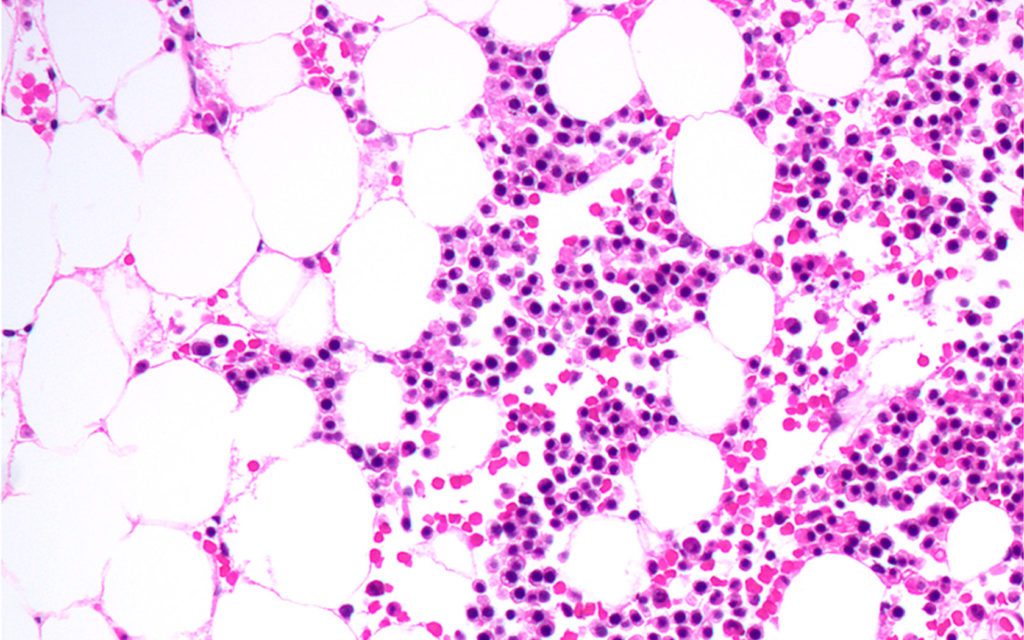

The first clinical study of a new drug designed to kill cancer cells by depriving them of the nutrients they need to survive is underway at MD Anderson. Named after MD Anderson’s Institute for Applied Cancer Science (IACS) where it was developed, IACS-10759 blocks the conversion of nutrients into the energy that fuels cancer cells.The study will enroll up to 48 patients with acute myeloid leukemia (AML) and is supported by a $3.5 million investment from The Leukemia & Lymphoma Society’s (LLS) Therapy Acceleration Program®.